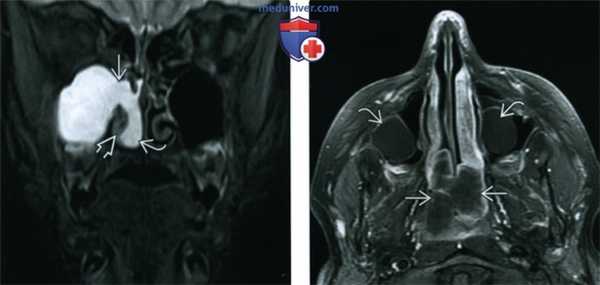

(Слева) При аксиальной МРТ Т2ВИ FS визуализируются гипоинтенсивные полипы, заполняющие решетчатые и основные пазухи и приводящие к их вздутию. На Т2 ВИ гипоинтенсивные полипы имитируют газ в пазухах.

(Справа) При сагиттальной МРТ Т1ВИ С+ у этого же пациента в полости носа визуализируются множественные полипы, накапливающие контраст. Полипы в основной пазухе характеризуются сигналом смешанной интенсивности. Обратите внимание на выраженное истончение кортикального слоя ската.